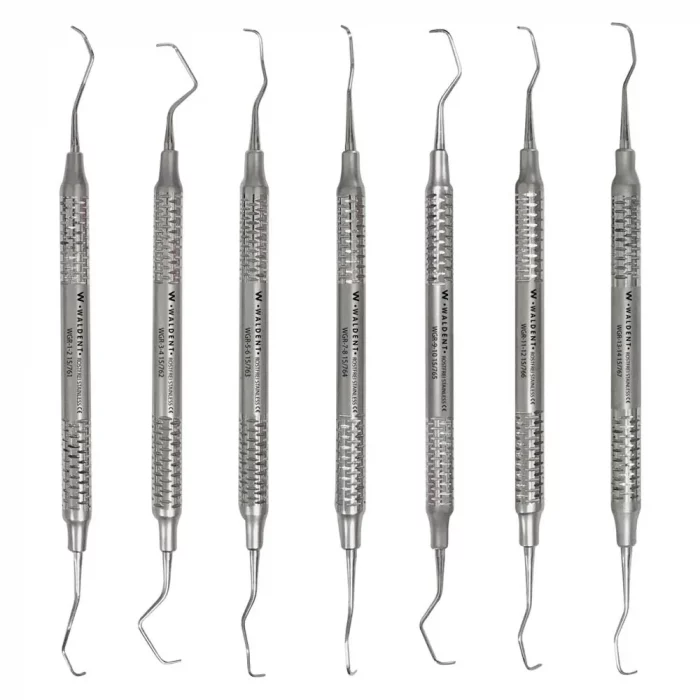

- Made from selective stainless steel

- Crafted using modern machines and skilled workers

- Area-specific instruments for subgingival scaling

- Offset blade at 70° angle

- Single cutting edge for precise scaling

- Long and short shanks for accessibility

- Hook-shaped toe for controlled insertion

- The Gracey 9/10 is predominantly used on the buccal and lingual molar aspects, especially around the bifurcation, where access can be difficult. Its wide contra-angle, wide return angle, and short shank make it a distinctive instrument. The toe is very nearly in line with the instrument handle, making this pattern especially suited to the least accessible root surfaces, while still allowing good control